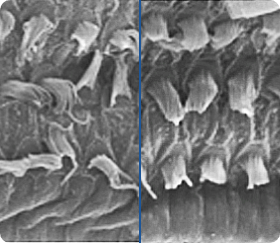

Mit den Fortschritten in Wissenschaft und Technik stellen sich die Forscher immer wieder die Frage, ob es möglich ist, ein Präparat herzustellen, das in der Lage ist, das Gewebe des Trommelfells und die Haarzellen der Cochlea zu erneuern. Denn die Zerstörung der Haarzellen führt zu einem teilweisen oder vollständigen Verlust des Hörvermögens - und ihre Wiederherstellung hat den Effekt, dass sich das Hörvermögen verbessert und die Schallwahrnehmung verbessert. Könnte die innovative Formulierung von Audiovico eine Chance bieten, die Zellen auf natürliche Weise wiederherzustellen und das Hörvermögen von Menschen mit Hörminderung zu verbessern?

Haarzellen bei Hörstörungen und nach der Hörverbesserung. / Bewegen Sie den Schieberegler, um den Unterschied zu sehen.